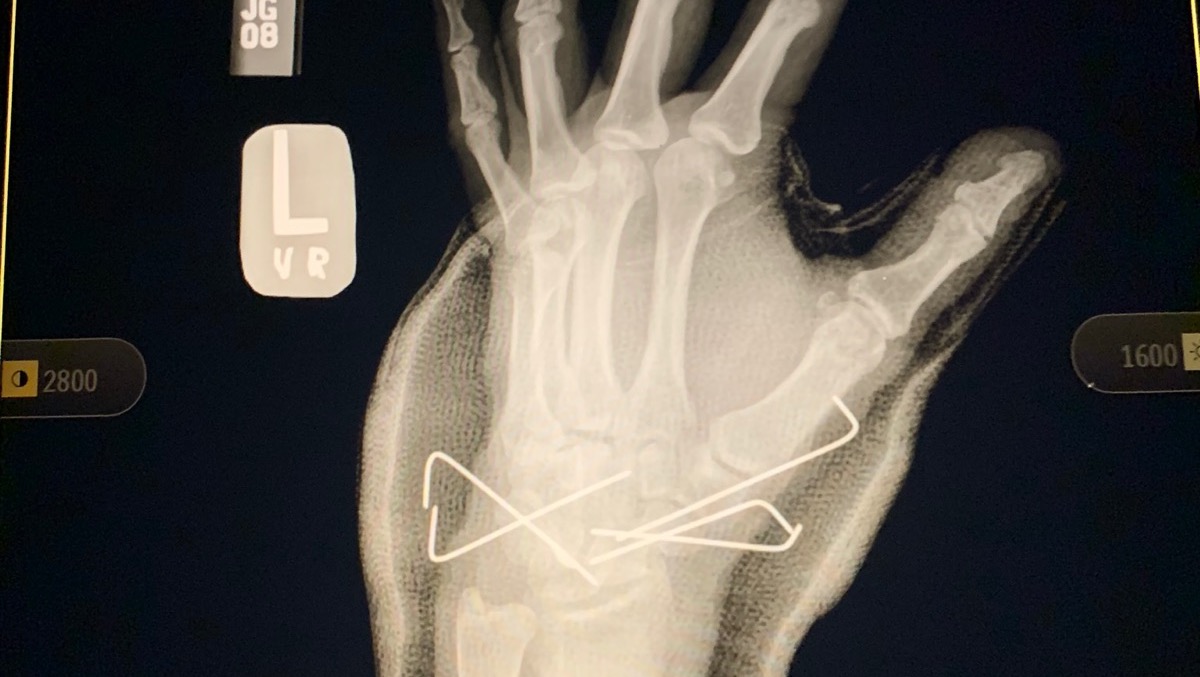

In 2007, I was in a near fatal accident and fell off of a 20 foot bridge. I was rushed to the hospital where they put me in a drug induced coma for two weeks. When I woke up I had an “external fixator” on my right leg and foot with rods and pins sticking out everywhere. My right tibia and fibula were broken and both feet were shattered. My left foot had a steel plate secured with seven screws. My right foot had an “Ex-fix” secured with rods and pins. My left wrist was shattered and required five pins to put back together. My back was broken as well and had to be fused together at L4-S1 with more rods and screws.